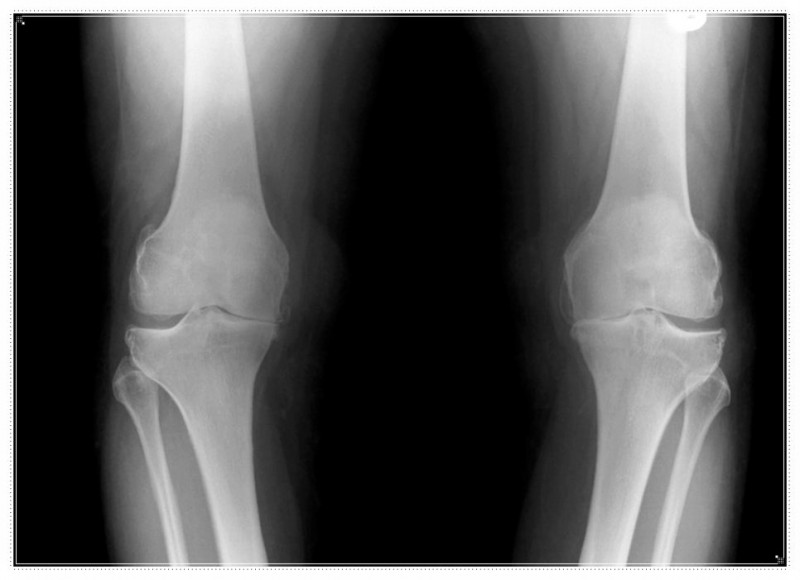

무릎의 불편함을 겪는 분들 중에는 휜다리, 평발, 혹은 무릎이 뒤로 과하게 꺾이는 반장슬과 같은 구조적인 문제를 이미 가지고 계신 경우도 적지 않습니다.

• 오래 서 있을 때 무릎 안쪽이 특히 더 아프거나, 신발 굽이 한쪽만 유독 빨리 닳지는 않으신가요?

• 혹은 똑바로 섰을 때 양 무릎 사이가 유난히 멀어 보이지는 않으신가요?

이러한 증상은 신체 정렬의 불균형을 알리는 구조 요청일 수 있습니다.